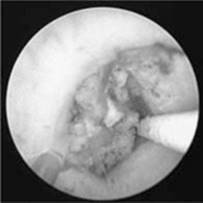

Methods of stone removal. Stone removal is largely an endoscopic procedure via the upper or lower urinary tract depending on the site of the stone, with or without the use of an energy source to shatter the stone prior to removal (Fig 9.4d). The other key method of removal is extracorporeal shock wave lithotripsy (ESWL, Fig 9.4e). Rarely is open stone removal required (open ureterolithotomy, pyelolithotomy or anatrophic nephrolithotomy). Laparoscopic surgery may now be used for difficult, large, impacted ureteric stones that cannot be manipulated up or down. The following methods are most frequently used in the operative management of urinary tract calculi.

Figure 9.4d URS/ureteroscopic view of stone

Reproduced with permission from John Kourambas

Cystoscopy and ureteroscopy with stone basket extraction is suitable for small calculi in the lower or intramural ureter that fail to pass despite persisting pain. Energy sources commonly used to fragment the calculi may include pneumatic lithotripsy or laser (holmium). The patient may require temporary stenting with a flexible, double J pigtail stent to guard against recurrence of colic from the oedema left by the stone itself or the procedure to remove it, which can be removed under local anaesthetic at a later date. Stent symptoms include frequency, urgency and loin pain, especially with voiding (stents cause reflux) and haematuria. Patients should be assessed for infection, bearing in mind a degree of red and white cell loss in the urine is consistent with the stent itself.